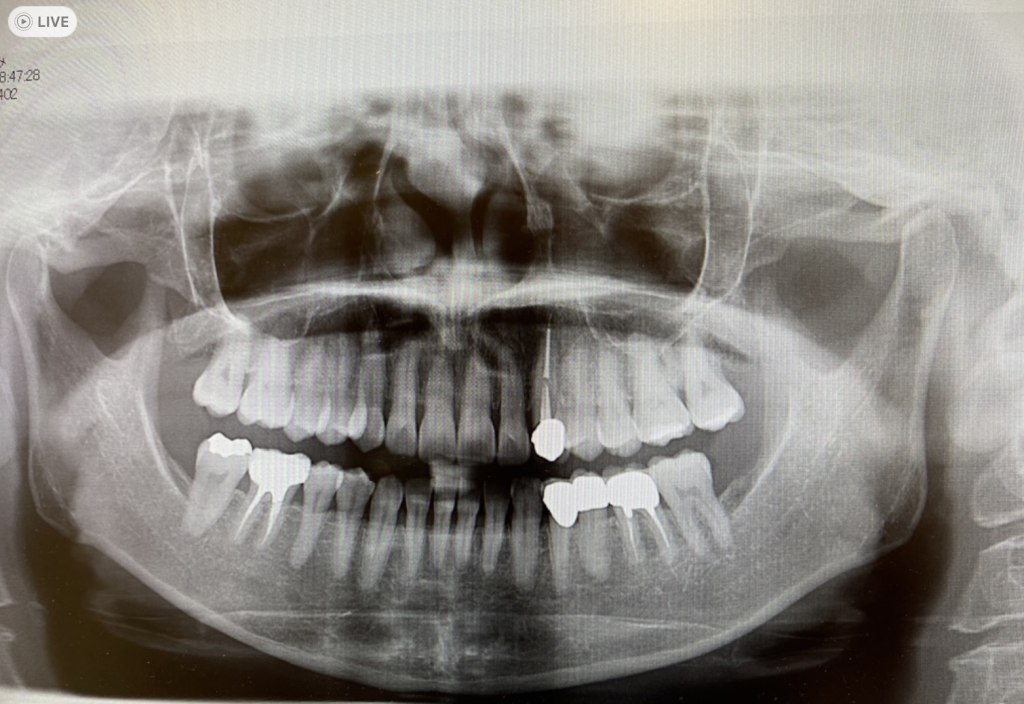

コーンビームCTは、立体(3D)のX線画像を取得できる歯科用CT装置です。

従来のレントゲンは平面画像のみでしたが、CBCTでは歯や顎の骨、神経の位置関係を詳細に把握でき、治療の計画や安全性が大きく向上しています。

歯周病では、歯を支える骨(歯槽骨)がどの程度失われているかを正確に知る必要があります。

CBCTなら骨の吸収範囲を立体的に診断し、治療計画を的確に立てられます。